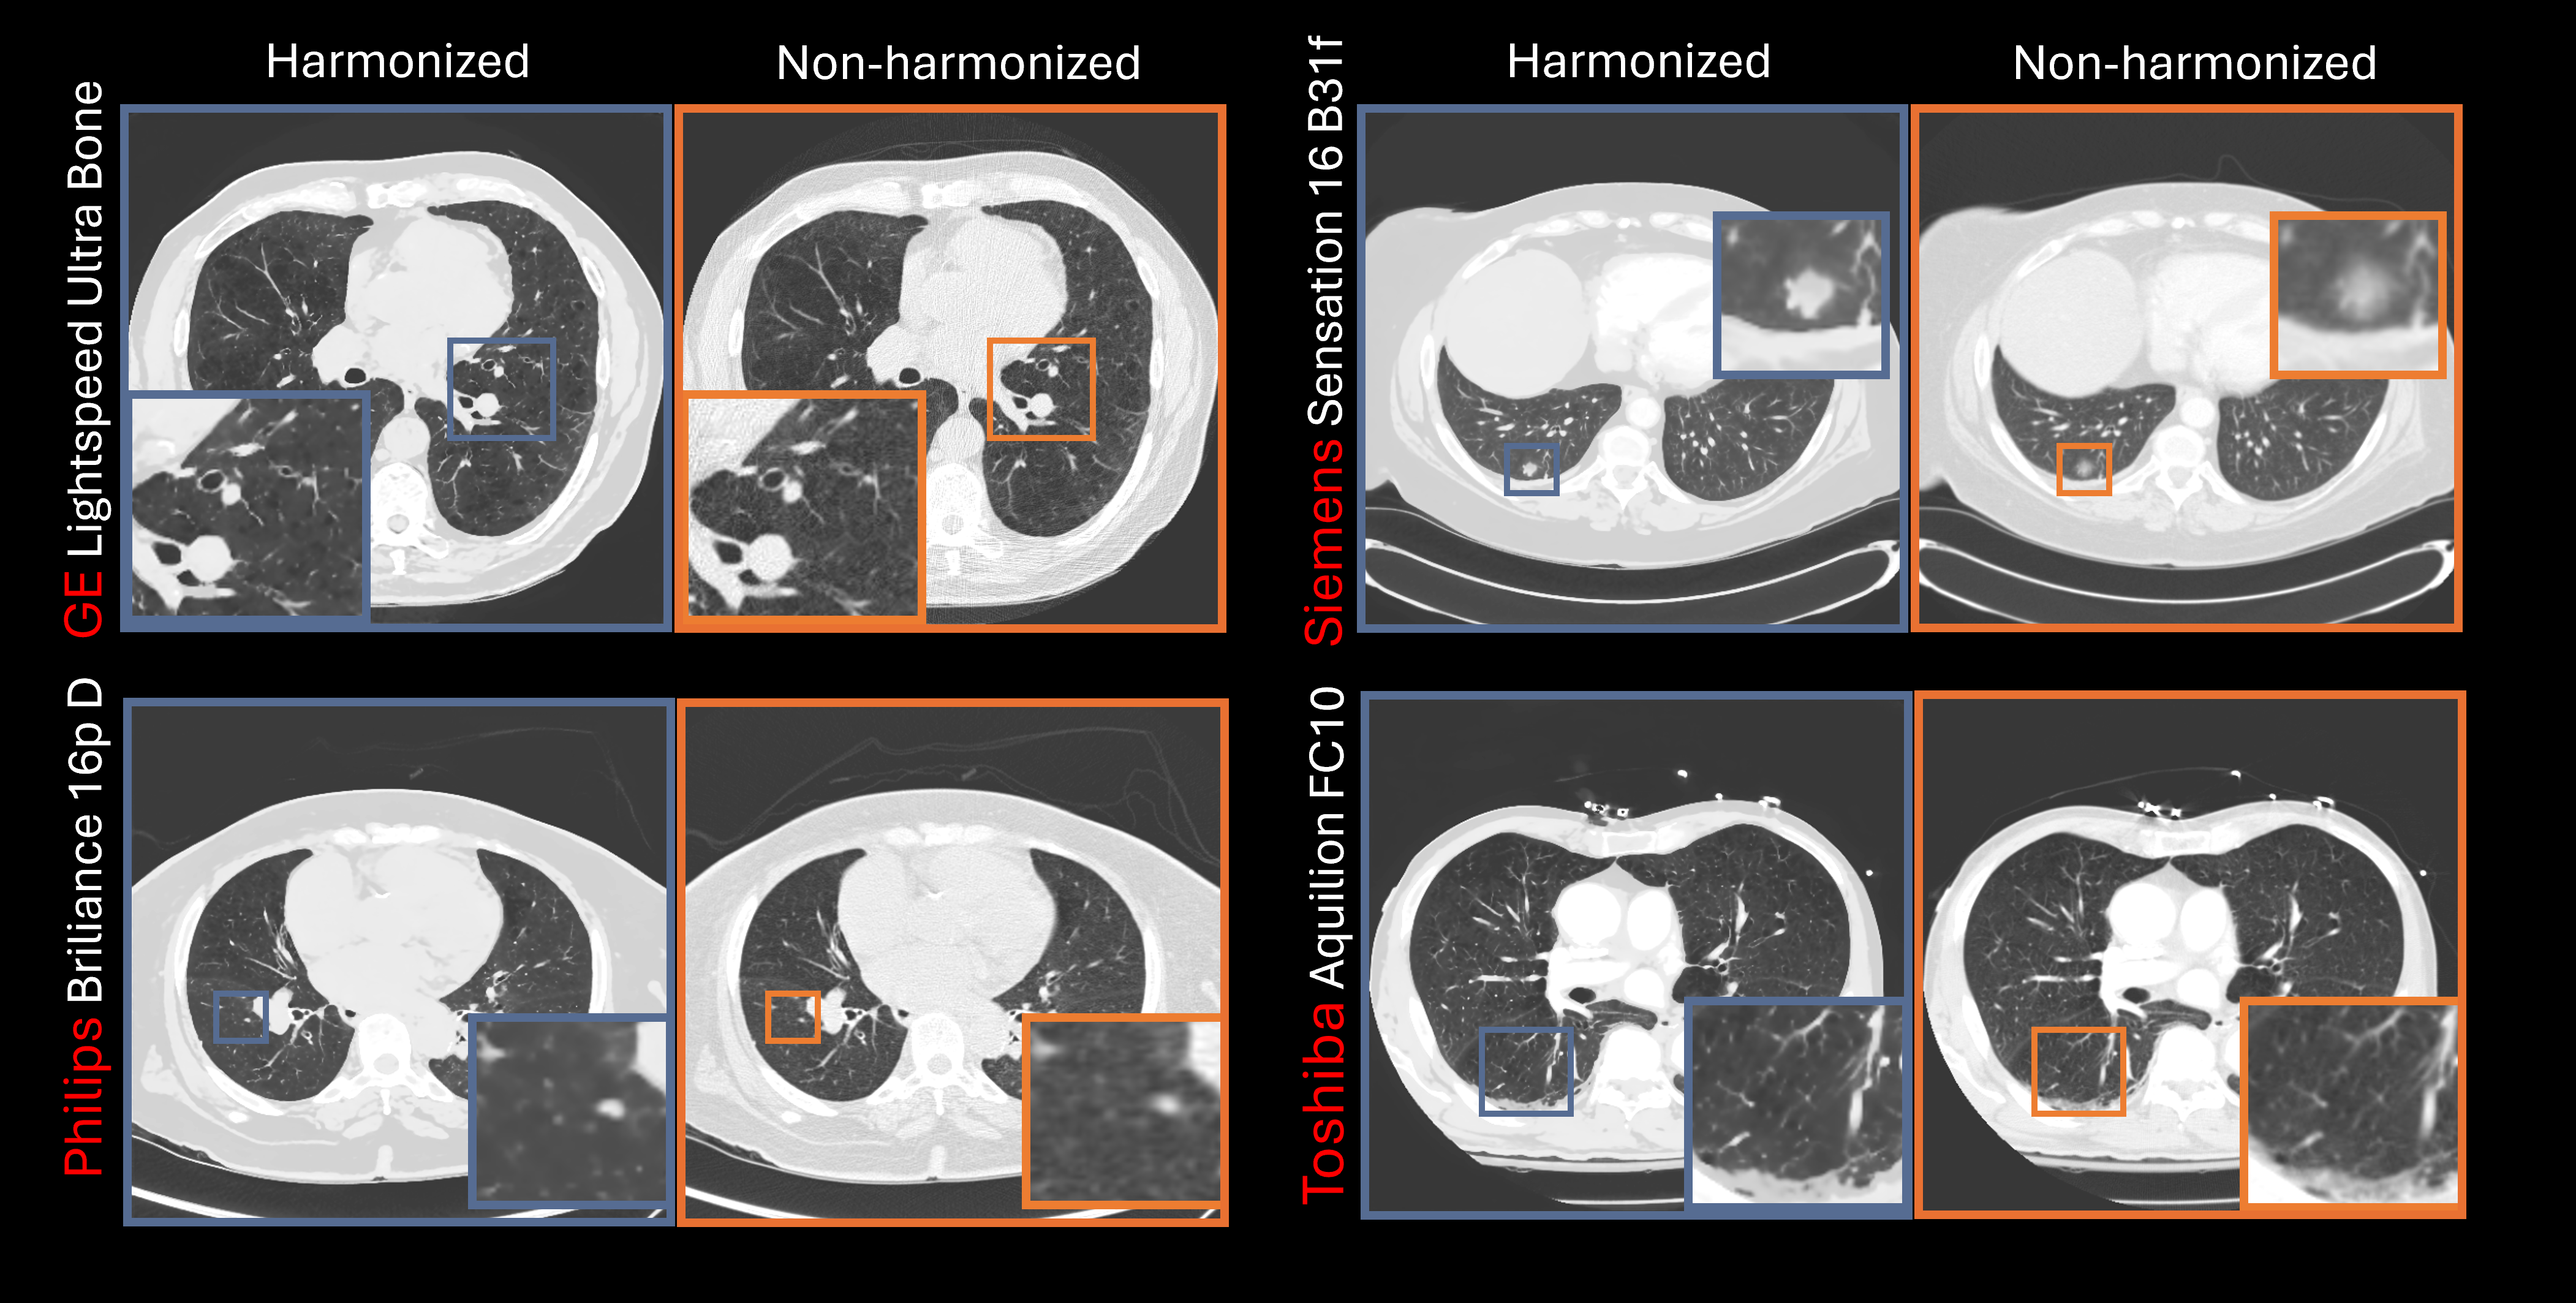

Medical images from different scanners often vary in texture and noise, complicating diagnosis. I developed Physics-Informed Deep Neural Networks that harmonize these images, making a scan from Scanner A look quantitatively identical to Scanner B.

• Generalizability: Unlike standard "black-box" AI, I injected physics constraints (noise power spectra, modulation transfer functions) into the training process and model architecture. This ensured the model learned the underlying physics of image formation, not just dataset correlations.

Figure: Comparison of clinical harmonized and non-harmonized CT images generated by a physics-informed GAN trained solely on digital twin data.